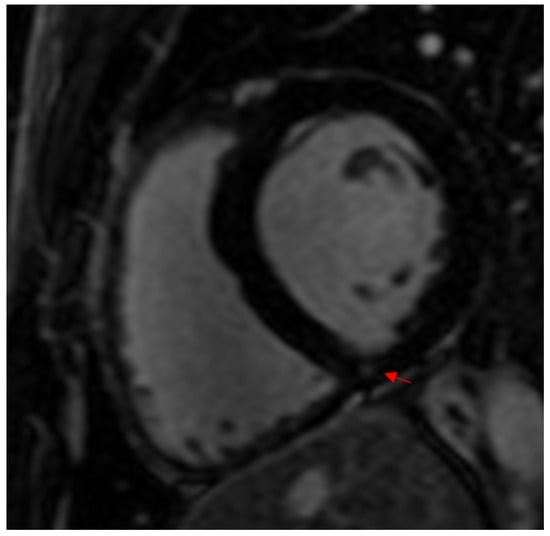

- Cummings, K.W.; Bhalla, S.; Javidan-Nejad, C.; Bierhals, A.J.; Gutierrez, F.R.; Woodard, P.K. A pattern-based approach to assessment of delayed enhancement in nonischemic cardiomyopathy at MR imaging. Radiographics 2009, 29, 89–103. [Google Scholar] [CrossRef] [PubMed]

- Wilson, M.; O’Hanlon, R.; Prasad, S.; Deighan, A.; MacMillan, P.; Oxborough, D.; Godfrey, R.; Smith, G.; Maceira, A.; Sharma, S.; et al. Diverse patterns of myocardial fibrosis in lifelong, veteran endurance athletes. J. Appl. Physiol. 2011, 110, 1622–1626. [Google Scholar] [CrossRef]

- Schnell, F.; Claessen, G.; La Gerche, A.; Bogaert, J.; Lentz, P.-A.; Claus, P.; Mabo, P.; Carré, F.; Heidbuchel, H. Subepicardial delayed gadolinium enhancement in asymptomatic athletes: Let sleeping dogs lie? Br. J. Sports Med. 2016, 50, 111–117. [Google Scholar] [CrossRef]

| Wilson et al. (2011) [20] 1.5 T | 29 12 lifelong veteran endurance and 17 young endurance: marathon, ultramarathon, ironman, triathlon | Veteran: 43 ± 6 y of competitive training Young: 18 ± 7 y of competitive training | 57 ± 6 31 ± 5 | M: 100 1.96 ± 0.14 2 ± 0.14 | Veteran: 6/12 (50%) Young: 0/17 Total: 6/29 (20.7%) | 1 CAD pattern: subendocardial septal and lateral wall infarction pattern 5 non-CAD pattern: 1 subepicardial lateral wall (myocarditis), 4 junctional: basal and mid insertion point, inferior insertion point and mid/apical, inferior mid/apical insertion point, inferior insertion point | - | - |

| Bosscher et al. (2020) [23] 3 T | 231 Elite endurance athletes | - | 18 ± 2 (young) 38 ± 5 (middle-aged) | M: 79 F: 21 | M: 27/187 (14.4%) F: 1/50 (2%) Total: 28 (12.5%) | M: 24 RV insertion points, 3 subepicardial LV lateral wall F: 1 RV insertion points | - | - |